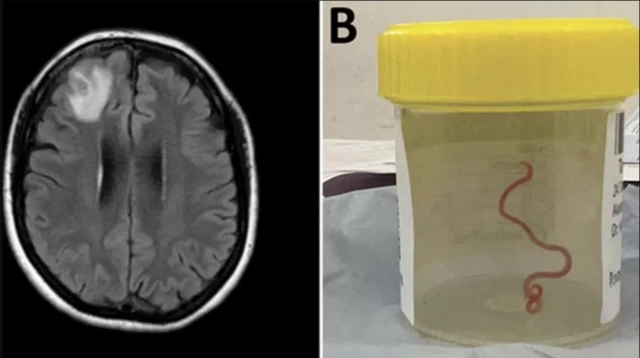

په نړۍ کې په لومړي ځل ساینسپوهانو ویلي، چې د یوې اسټرالیایۍ ښځې په ماغزو کې ۸ سانتي متره (۳انچه) چینجی ژوندی موندل شوی دی.

"د تار په شان جوړ" دا چینجی تېر کال کینبیرا کې د جراحۍ پر مهال د ناروغې ښځې د ماغزو له مخکنۍ برخې رایستل شوی و.

د کینبیرا روغتون کې د میکروبي ناروغیو یوه ډاکټر سنجایا سینانایاک وویل: "هر یوه په عملیاتي ځای کې ټکان وخوړ چې جراح په غیر عادي حالت کې ۸ سانتي متره روښانه سور چینجی غوندې یو څه ولیدل."

ناروغه ښځه د ۲۰۲۱ کال د جنورۍ وروستیو کې روغتون کې بستري شوې وه. د هغې د ماغزو سکن د مغز په مخکنۍ ښۍ خوا کې یو غیر عادي څه وښودل، خو د ۲۰۲۲ تر جون میاشتې (د جراحۍ له پیلېدو پورې) هېچا ته پته نه لګېده چې دا به څه وي.